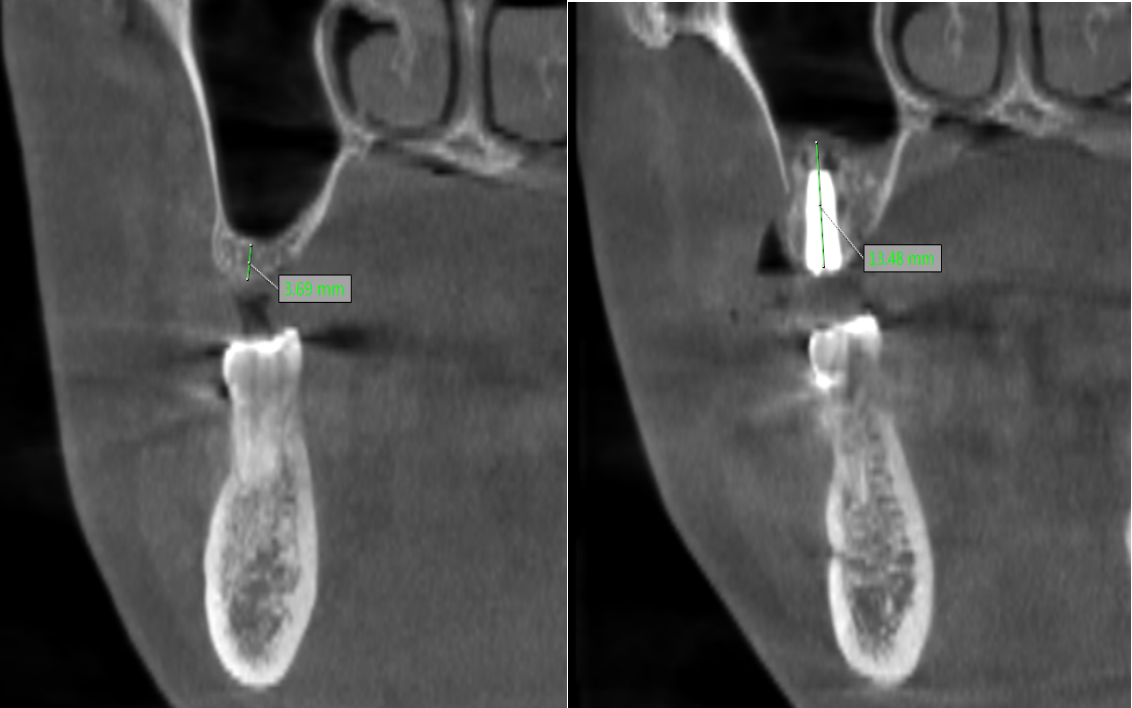

种植牙成功的核心在于充足的骨量支撑,对于骨量严重不足的患者,术前精准评估与科学规划非常重要。口腔科闫慧鑫主任带领团队,结合患者全身健康状况、口腔功能需求及美学期待,运用三维 CBCT 影像技术对颌骨进行全方位、立体化扫描分析。通过精准测量剩余牙槽骨的高度、宽度,明确上颌窦位置与形态,同时模拟手术全过程与修复效果,最终为患者制定了上颌窦外提升同期种植体植入的个性化手术方案,让每一份骨量都能得到充分利用。

手术中,闫慧鑫主任带领团队将数字化导航技术、微创理念与精准外科操作深度融合,在确保上颌窦开窗完整、黏膜剥离无损的前提下,小心翼翼分离并提升上颌窦黏膜,再精准植入骨材料以增加骨高度,为种植体植入创造理想条件,随后顺利完成了骨材料植入与种植体植入。